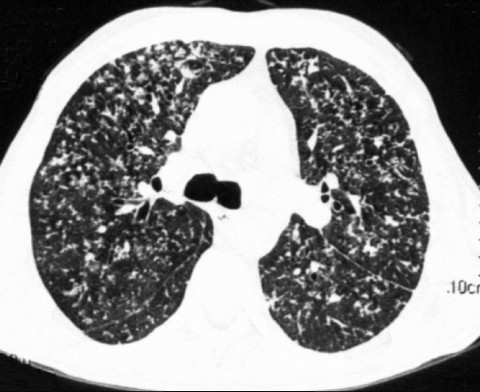

На КТ-снимках очаговые изменения могут выглядеть, как затемнения округлой/размытой формы или осветленные зоны. Так, одним из осложнений при хроническом бронхите может быть увеличение воздухосодержащих пузырьков. При проведении КТ эмфизема легких  визуализируется в виде нарушения легочного рисунка и распространения зон «прозрачности». Здоровая легочная ткань имеет плотную структуру с четко очерченными краями, в то время как участки с эмфиземой отличаются повышенной воздушностью.

Очаговые поражения при туберкулезе имеют вид «матового стекла» и сопровождаются увеличением лимфоузлов. При наличии подобных изменений в ходе рентгенографического обследования по КТ легких пневмония дифференцируется от первичного туберкулеза. Сканирование обнаруживает уплотнения, обсеменения или участки распада в легких диаметром от 1 мм, что дает возможность раннего распознавания болезни.